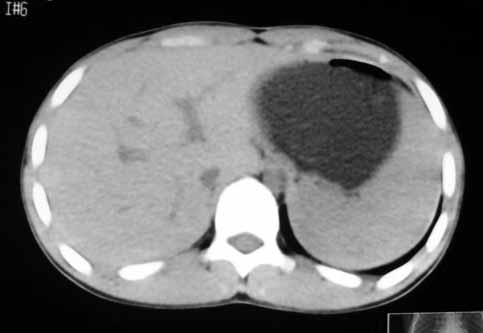

以下是引用zhangzhongshou在2007-5-22 21:04:00的发言:[br]1、脾肿大[br]2、脾脏低密度影,血管瘤?脾梗塞不能除外,建议增强扫描。

以下是引用dyqct在2007-5-22 20:45:00的发言:[br]巨脾,可疑梗塞,建议增强、查血象进一步检查

以下是引用liuyue在2007-5-23 7:57:00的发言:[br]腹主动脉周多个肿大淋巴结,脾大伴三角形低密度影,肠腔积气,考虑:1淋巴瘤2脾大伴梗塞3肠腔积气(肿大淋巴结压迫所致)